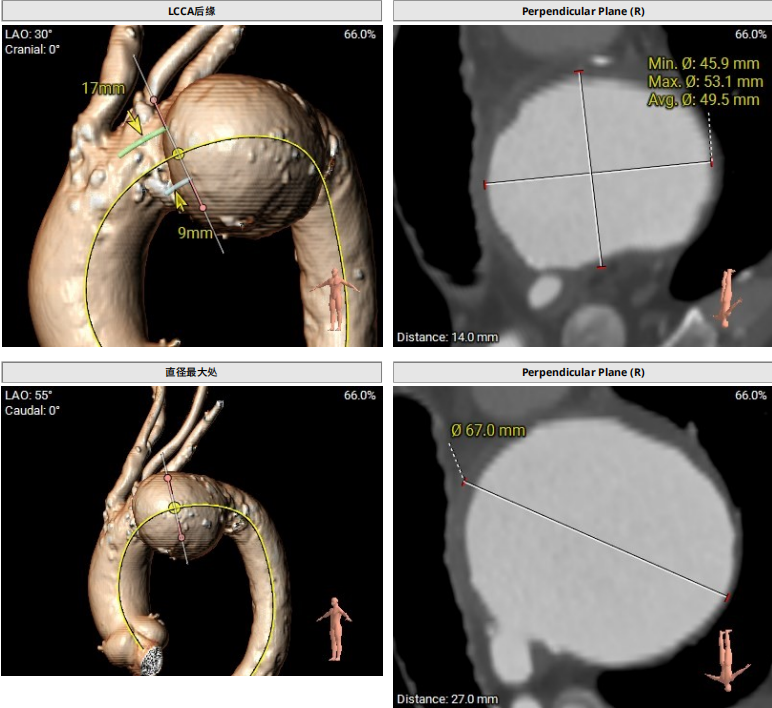

该患者主动脉弓部瘤,瘤体起始于LCCA前缘,距IA后缘4mm(小弯侧),瘤体最大处直径67mm,左椎优势。

CTA显示,患者主动脉弓部瘤,瘤体起始于LCCA前缘,距IA后缘4mm(小弯侧),瘤体最大处直径67mm

术后一周患者返院进行常规随访检查。CTA检查结果显示:植入支架与血管壁贴合良好,未见内漏征象。患者术前巨大动脉瘤瘤囊已完全血栓化,瘤腔内血流信号消失。